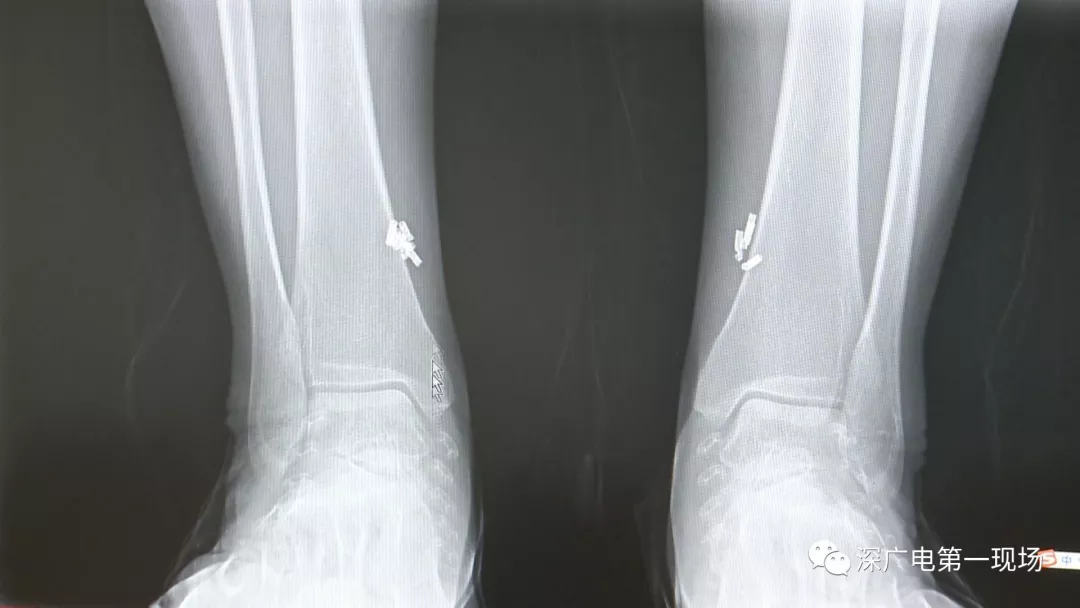

深圳一女子全身被植入彈簧圈,數(shù)量多到驚人!竟是為治這病…

出于保護(hù)患者,我們沒有直接采訪,但是通過醫(yī)生的介紹,記者了解到,病人是個(gè)36歲的女性,2歲開始就有癲癇病史,而且藥物治療也并不見效。

多方打聽之后,在山東某診所用全身埋彈簧圈的方式治療癲癇。陶主任介紹,這樣的方式想要治愈,那幾率也等同于撞大運(yùn)?。?/p>